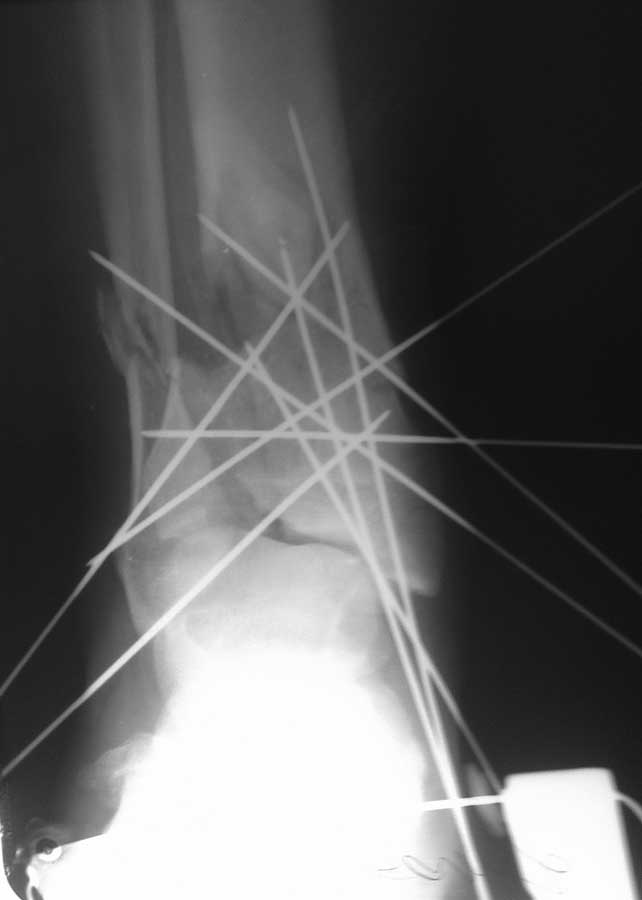

Отрытый многооскольчатый перелом ДЕМ большеберцевой кости правой голени. Больному 65 лет.

Гиперстеник. Сопутствующий варикоз вен нижних конечностей При поступлении поперечная

рана по передне-медиальной поверхности н/з голени длиной до 7 см. Выполнено ПХО раны,

открытая репозиция отломков с фиксацией спицами выведеными чрескожно, наложена система

скелетного вытяжения. На данный момент заживление раны per secunda. У нас два варианта:

продолжение ведения больного на скелетном вытяжении с гипсованием на 6-8 неделе или

наложение апарата внешней фиксации. Ваши предложения по поводу дальнейшей тактики

ведения.